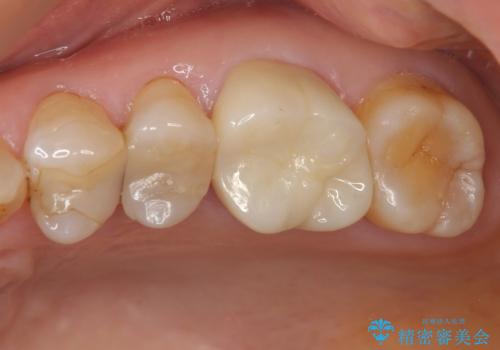

- ブリッジの歯のないところにインプラントを入れて、銀歯を白くやり替えたいと来院された患者様です。

歯の欠損している箇所にはインプラント治療をし、銀歯と仮詰めの部分はセラミックインレーにて補綴することとしました。